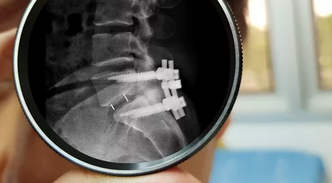

🔪 3. 척추유합술 (심한 디스크 탈출증 또는 척추 불안정성 동반 시)

✔ 손상된 디스크를 제거한 후, 척추 뼈를 금속으로 고정

✔ 회복 시간이 길고, 수술 후 재활이 중요